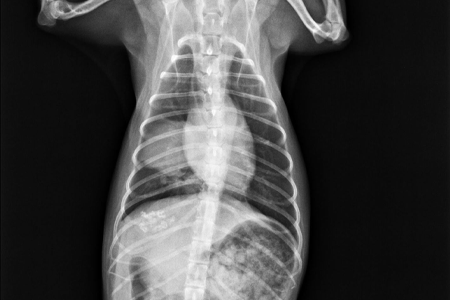

レントゲン検査では原発性肺腺癌は多くは孤立性を示します。また、腫瘍の多くは結節性間質パターンを示します。

肺腫瘍